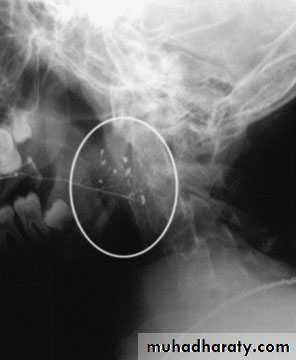

Parotid stone :

Much rare than submandibularUsually radiolusent .

Sialography

Stone removed surgically either by exposing duct or parotidectomy approach.